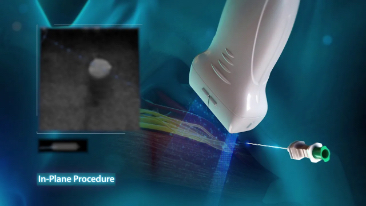

Mindray, ?irketin kuruldu?u gĂŒnden bu yana sĂŒrekli olarak tan?sal do?rulu?u iyile?tirmeye ?al??maktad?r. Devrim niteli?indeki ZONE Sonography? Teknolojisi ile desteklenen Resona 7ânin yeni ZST+ platformu, b?lge g?rĂŒntĂŒsĂŒ alma ve kanal veri i?leme ?zellikleri ile ultrason g?rĂŒntĂŒsĂŒ kalitesini daha ĂŒst bir dĂŒzeye ??kar?yor.